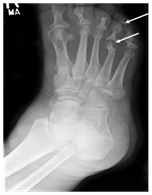

The preliminary assessment should include patient’s history of complete symptoms like, malaise, fever, and lethargy, backache along with predisposing factors like trauma or use of drugs through intravascular route. Main focus of investigation must be on finding a possible suspected locus of infection. Sterilised steel probe is useful to identify osteomyelitis in contagious infection such as diabetic foot. Lavery LA et al.19 Finding revel that the reliability of this has been found to be 89 %, whereas only 57%, positive predictive value has been noticed in a population with lower prevalence of osteomyelitis.19 It is quite difficult to specify particular curative pathogenic organism responsible for osteomyelitis. Specific culture or microbiological testing is required to identify the pathogen such as mycobacterial, fungal and anaerobic organism20 (Figure 2).

Figure 2 Radiograph showing osteomyelitis among metatarsal and phalanges.